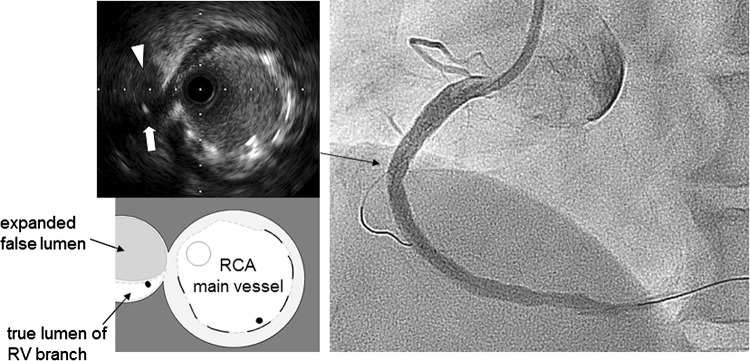

Fig. 2.

Angiogram after stenting showed that the right ventricular (RV) branch remained completely occluded. Intravascular ultrasound image from the right coronary artery main vessel at the RV branch bifurcation revealed that the RV branch was detected at 9 o’clock position. The true lumen of the RV branch (white arrow) was collapsed by an expanded false lumen that was presented as a high echogenic lumen (white arrowhead)